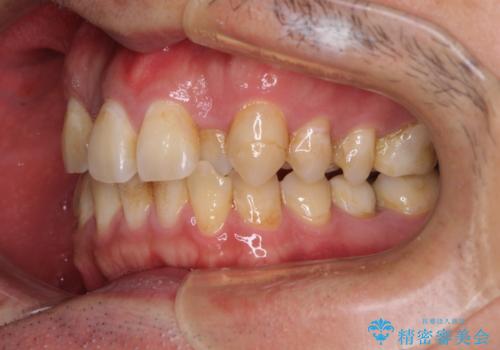

- 虫歯が多く、セラミッククラウンにより虫歯治療を行っている途中で矯正治療をしたいとのことで来院された患者様です。

上顎前歯が舌側に転位しており、なるべく早く楽に矯正したいとのことで、ワイヤー矯正を行うこととしました。